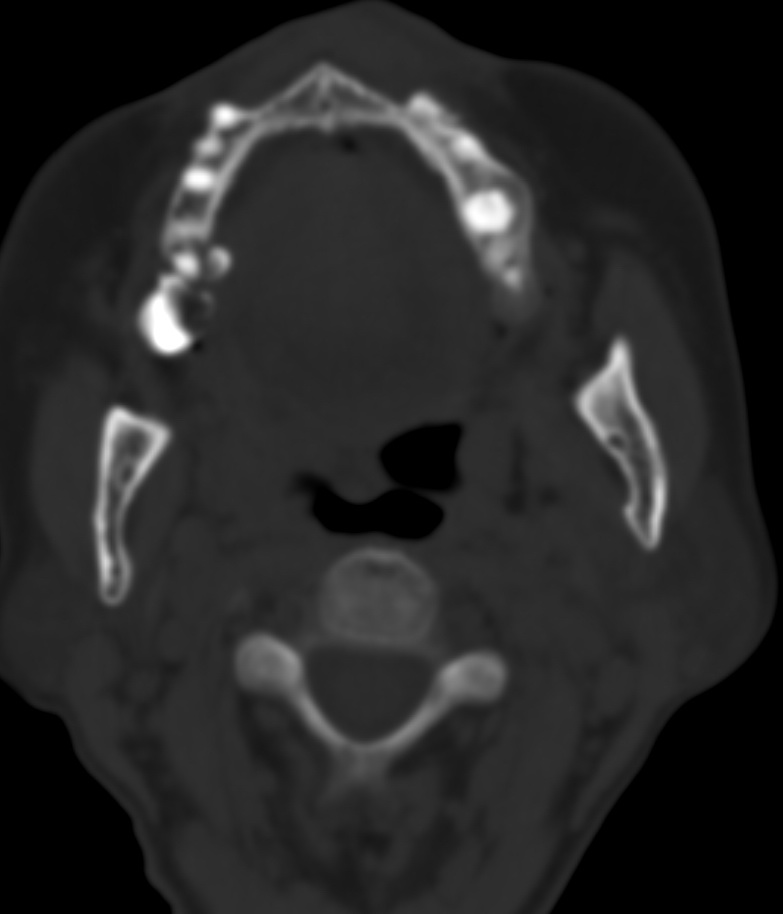

女,68岁。发现上唇无痛性肿块2年多,查体局部皮肤隆起,其余未见异常。

病灶ct值约42hu。